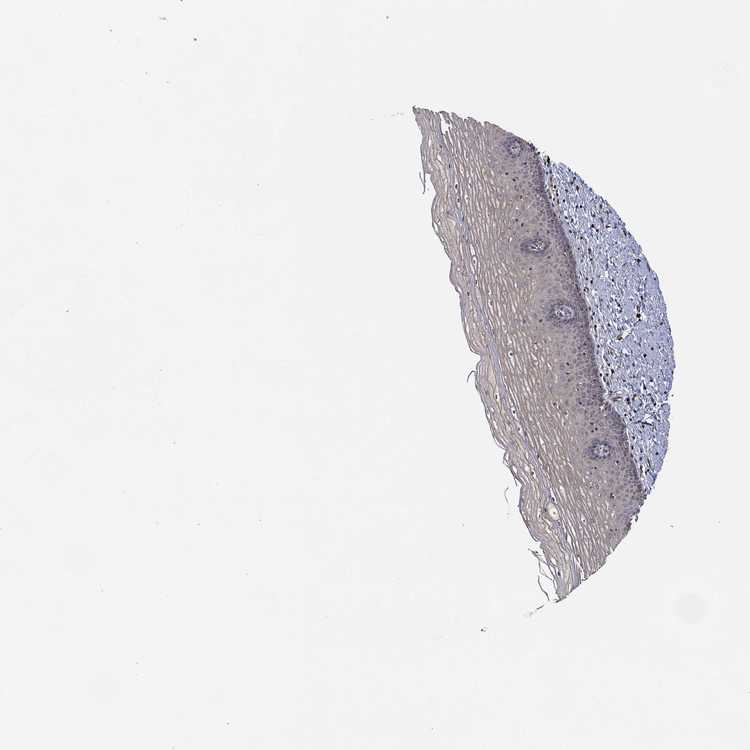

CERVIX - Antibody stainingi

Antibody staining in the annotated cell types in the current human tissue is reported as not detected, low, medium, or high, based on conventional immunohistochemistry profiling in selected tissues. This score is based on the combination of the staining intensity and fraction of stained cells.

Each image is clickable and will lead to virtual microscopy that enables deeper exploration of all samples and also displays staining intensity scores, fraction scores and subcellular localization as well as patient and tissue information for each sample.

Antibody HPA071736

Squamous epithelial cells Low